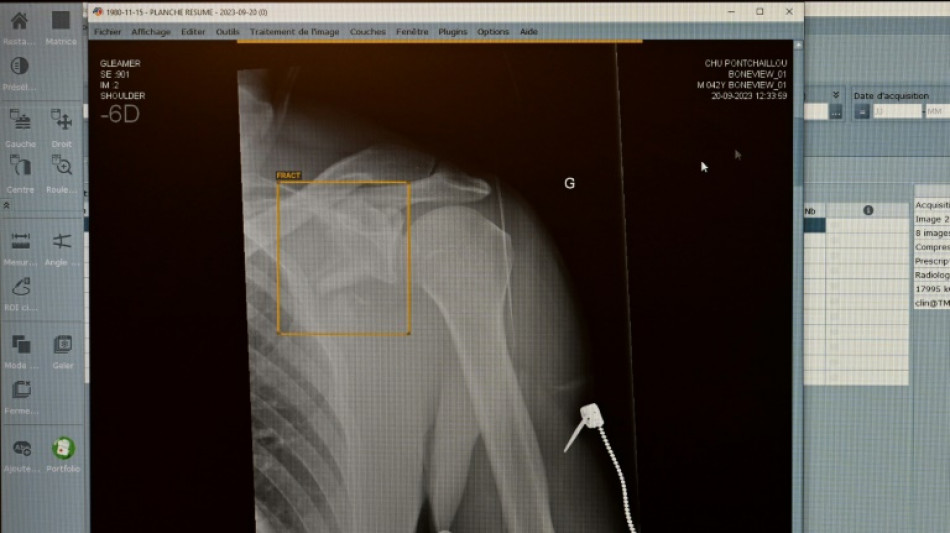

TÜV-Verband: Weniger Röntgengeräte mit Mängeln - Risiken bleiben aber / Foto: Damien MEYER - AFP/Archiv